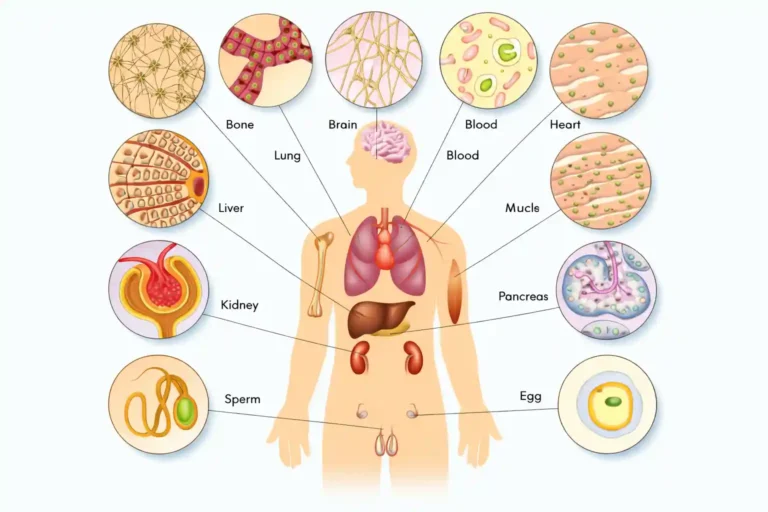

Applications of Stem Cell Therapy

Application of stem cell therapy include regenerative medicine, orthopedic neurological and hematopoietic disorders, ocular and cardiovascular diseases, skin and wound healing, diabetes management, liver diseases, and autoimmune disorders.

-

Regenerative Medicine:

Heart disease, spinal cord injuries, diabetes. -

Orthopedic Treatments:

Osteoarthritis, Sport injuries. -

Neurological Disorders:

Parkinson’s, Alzheimer’s multiple Sclerosis. -

Hematopoietic Disorders:

Leukemia, Lymphoma, Severe anemia. -

Ocular Diseases:

Retinal Damage, macular degeneration.